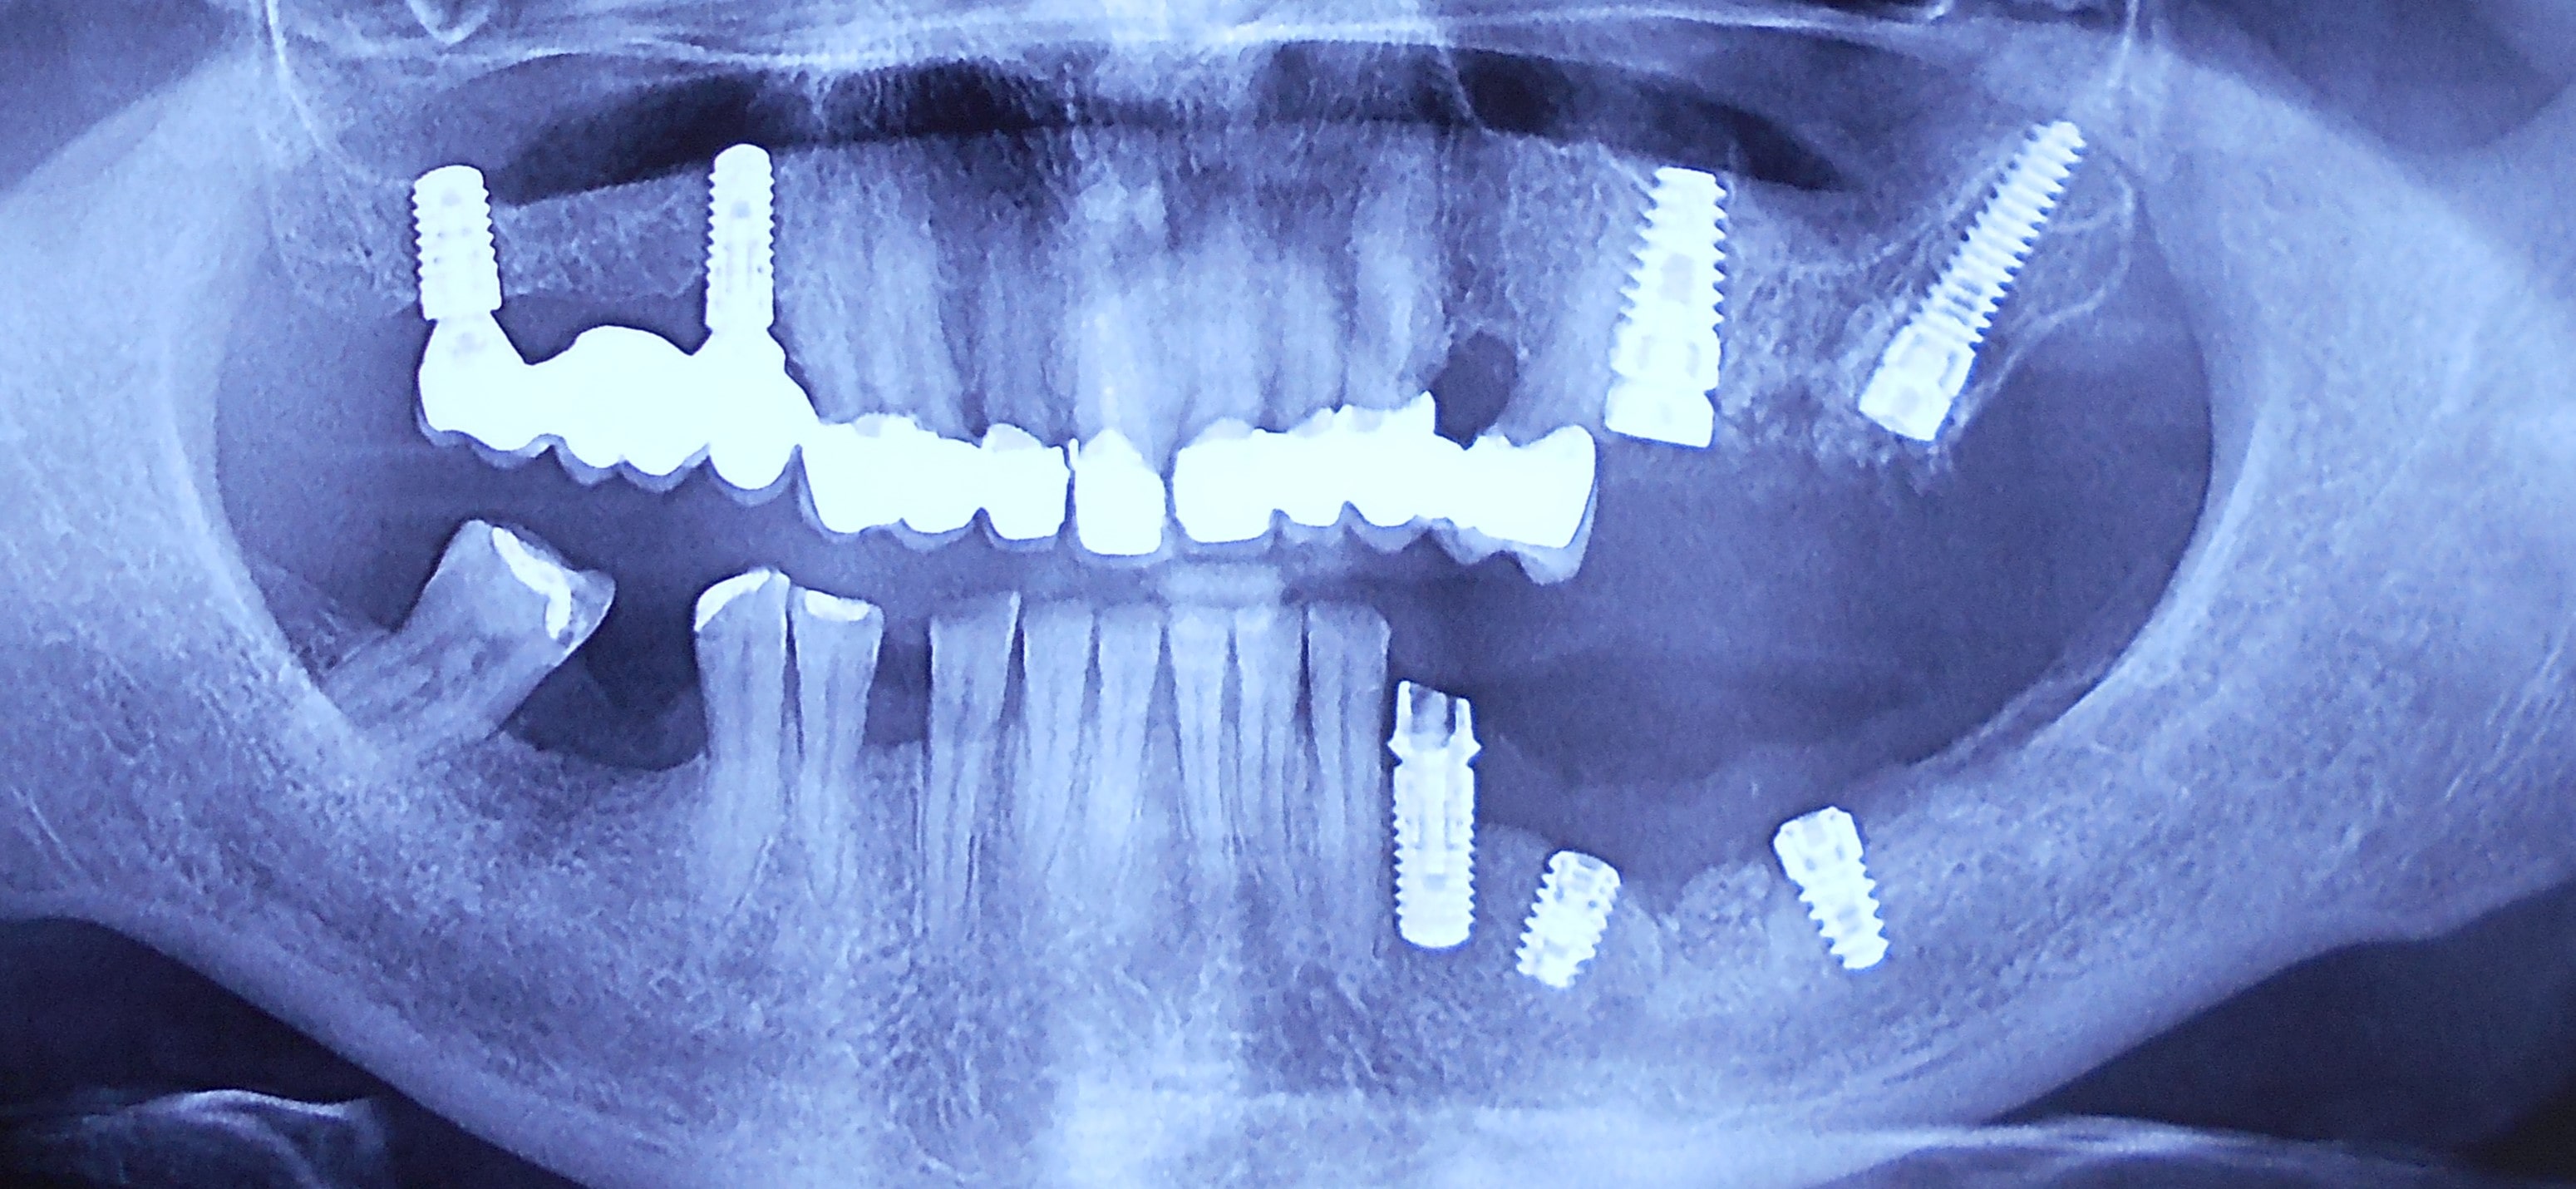

Pacijent iz Nemačke, kod koga smo estetsko i funkcionalno zbrinjavanje rešili cirkonijum keramičkim krunicama sa ugradnjom kratkih implantata u donjoj vilici zbog smanjene visine kosti, a u gornjoj vilici na levoj strani odmah nakon vađenja zuba je ugrađen standardni implantata na mesto izvađenog zuba i ugrađen je tuberopterigoidni implantat da se ne bi radila komplikovana sinus lift procedura koja bi produžila vreme završetka rada na godinu i više dana. Rad uspešno završen i pacijent nema nikakvih problema već pet godina.

Pacijent sa obe strane gornje vilice je bio bezub, sa minimalnom horizonatlnom i vertikalnom visinom kosti kao i sa spuštenim sinusom. Nakon dužeg traženja rešenja za svoj slučaj u drugim ordinacijama da bi izbegao komplikovanu sinus lift proceduru prihvatio je naš predlog da se ugrade po tri implantata sa obe strane gornje vilice od kojih su dva tuperopterigoidna implanta, koji su rešili problem spuštenog sinuasa sa minimalnom traumom prilikom ugradnje. Slučaj rađen pre četiri godine. Na poslednjoj kontroli izgleda besprekorno.

Pacijent iz inostranstva doalzi sa totalnom protezom u gornjoj vilici i sa uznapredovalom parodontopatijom preostalih zuba u donjoj vilici. Pacijent navodi da su mu u inostranstvu rekli da je nemoguće u gornjoj vilici ugraditi implantate bez velikih hirurških zahvata koji podrazumevaju transplantaciju kosti sa udaljenih delova tela i sinus lift proceduru. U gronjoj vilici je bila minimalna količina kosti sa izraženo spuštenim sinusima i sa minimalno vretikalnom i horizontalnom visinom kosti. Naše rešenje se sastojalo u sledećem: ugradnja deset implantata u gornjoj vilici u raspoloživu kost sa ugrdnjom veće količine veštačke kosti, od deset ugrađenih implanta dva implantata su tuberopterigoidna koji su zamenili sinus lift proceduru. U gornjoj vilici smo se opredelili za ugradnju većeg broja implantata kako bi prilikom izrade fiksnog protetskog rada dobili ravnomeran prenos pritiska žvakanja na implantate. U donjoj vilici intervencija je bila istovremena i ona je podrzumevala vađenje svih preostalih zuba i ugradnju osam implantata. Kompletno zbrinjavanje koje obuhvata hiruršku i protetsku fazu je trajalo tri meseca, tokom kojih je pacijent u gornjoj vilici bio zbrinut sa privremenom totalnom protezom, a u donjoj vilici sa fiksnim privremenim zubima koji su bili fiksirani na tek ugrađenim implantatima. Definitivni protetski rad je uspešno završen sa cirkonijum keramičkim - bezmetalnim mostovim pre četiri godine.